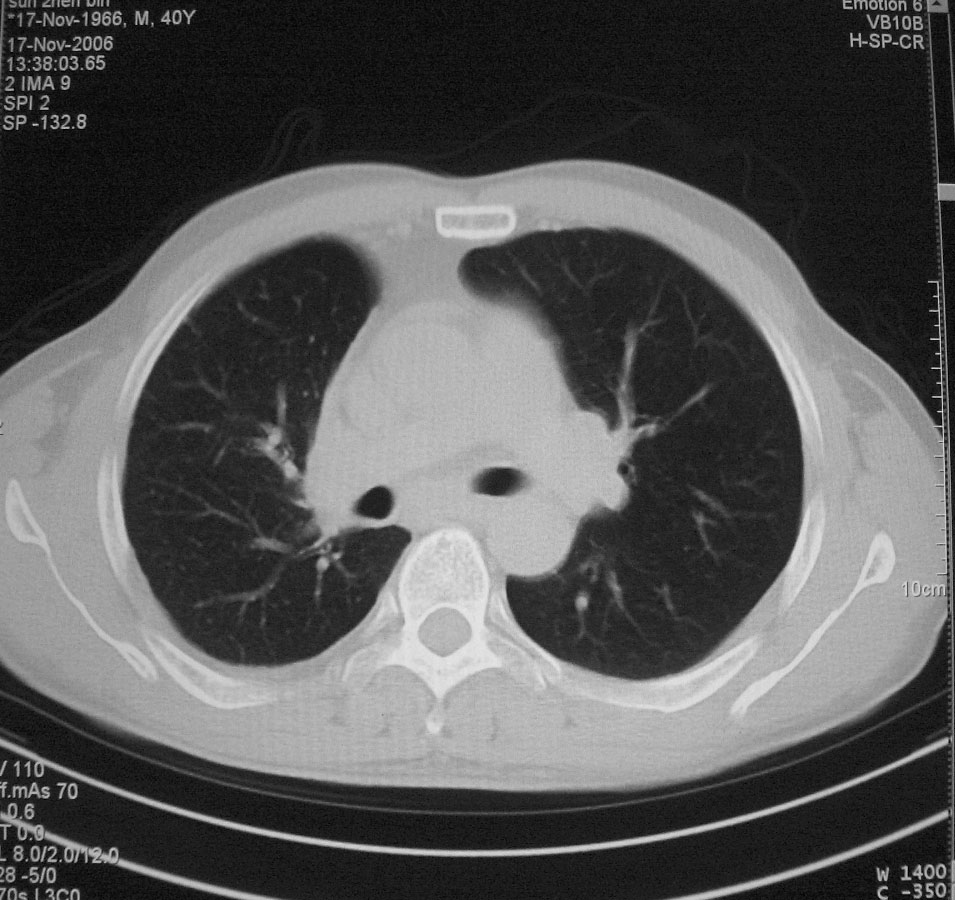

标题: CT5485:[原创]肺部占位请讨论

右上肺ca并肺不张,纵隔淋巴结转移

右肺上叶中央型肺癌并上叶肺不张、纵隔淋巴结肿大

右上叶支气管后壁明显增厚,支持右肺上叶中央型肺癌伴右上叶肺不张、纵隔淋巴结肿大。

右上叶支气管后壁明显增厚,支持右肺上叶中央型肺癌伴右上叶肺不张、纵隔淋巴结肿大。建议支气管镜检查。

右上肺中央性肺癌伴右侧胸腔少量积液!右上肺胸膜下还有一小病灶,不完全排除结核,但个人支持恶性肿瘤!建议早穿刺活检。

右上叶支气管开口变窄,纵隔见肿大的淋巴结。支持右上叶中心型肺癌并右上叶不张纵隔淋巴结肿大。

右肺上叶中央型肺癌并上叶肺不张、纵隔淋巴结肿大.右侧少量胸腔积液。

右肺上叶支气管后壁增厚,呈鼠尾状狭窄,纵隔内未见明显增大的淋巴结影,考虑为中央型肺癌伴右上肺不张